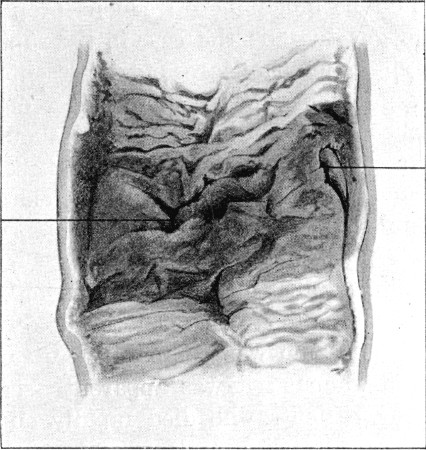

87. Entry and Exit Wounds in a Transverse Perforation of Intestine418

88. Inner Aspect of Piece of Intestine Shown in Fig. 87419